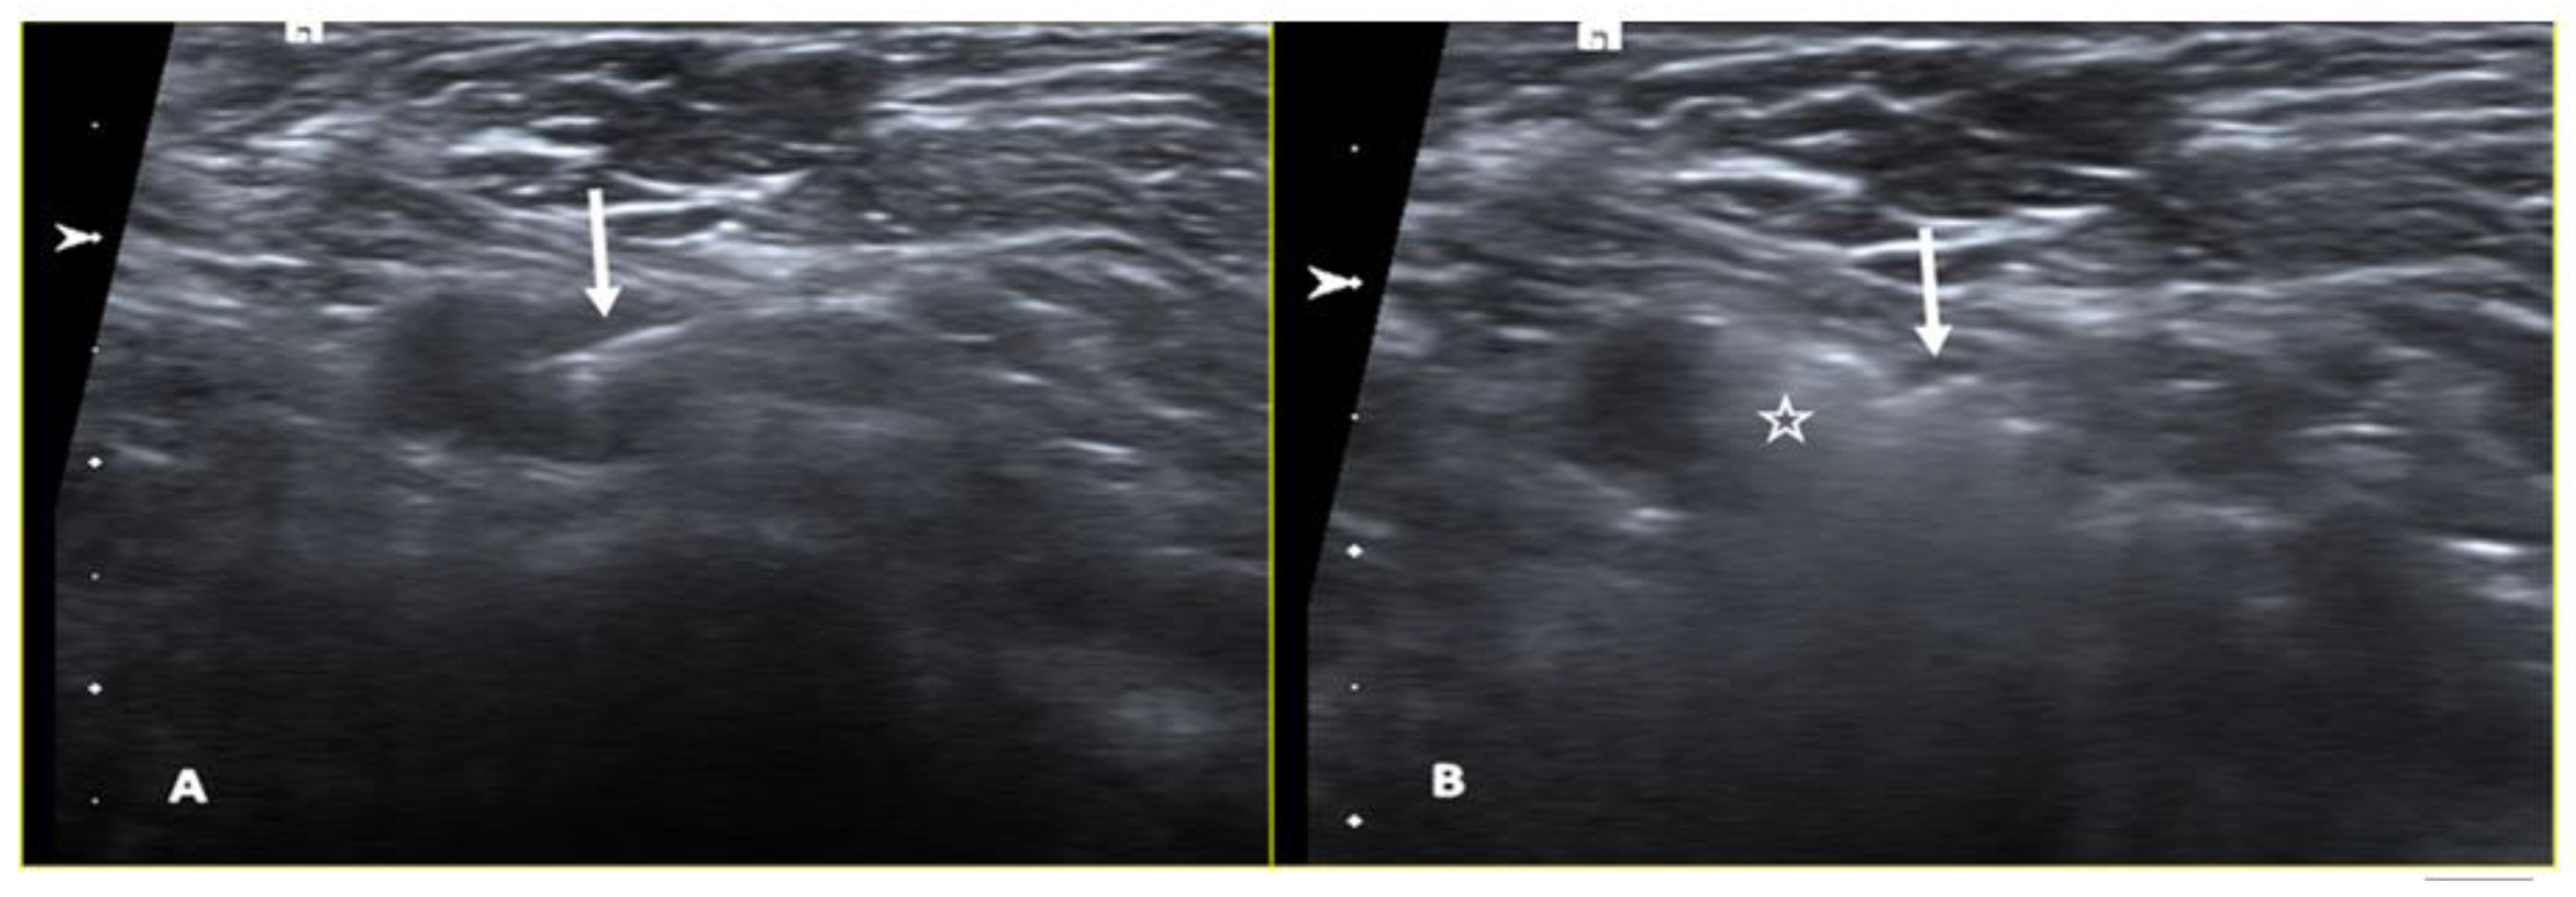

2.4. Magnetic Seed

- Harvey, J.R.; Lim, Y.; Murphy, J.; Howe, M.; Morris, J.; Goyal, A.; Maxwell, A.J. Safety and Feasibility of Breast Lesion Localization Using Magnetic Seeds (Magseed): A Multi-Centre, Open-Label Cohort Study. Breast Cancer Res. Treat. 2018, 169, 531–536. [Google Scholar] [CrossRef] [PubMed]

- Price, E.R.; Khoury, A.L.; Esserman, L.J.; Joe, B.N.; Alvarado, M.D. Initial Clinical Experience With an Inducible Magnetic Seed System for Preoperative Breast Lesion Localization. AJR Am. J. Roentgenol. 2018, 210, 913–917. [Google Scholar] [CrossRef]

- Mariscal Martínez, A.; Vives Roselló, I.; Salazar Gómez, A.; Catanese, A.; Pérez Molina, M.; Solà Suarez, M.; Pascual Miguel, I.; Blay Aulina, L.; Ríos Gozálvez, C.; Julián Ibáñez, J.F.; et al. Advantages of Preoperative Localization and Surgical Resection of Metastatic Axillary Lymph Nodes Using Magnetic Seeds after Neoadjuvant Chemotherapy in Breast Cancer. Surg. Oncol. 2021, 36, 28–33. [Google Scholar] [CrossRef]